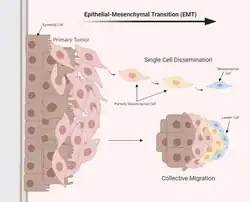

Transition épithélio-mésenchymateuse

La transition épithélio-mésenchymateuse est le processus d'acquisition des cellules épithéliales qui développent la capacité d'envahir, de résister et de se disséminer[12]. Les cellules épithéliales sont étroitement liées les unes aux autres et à la matrice extracellulaire[13]. La transition épithélio-mésenchymateuse régit les altérations biochimiques réversibles qui permettent à une cellule épithéliale d'atteindre un phénotype mésenchymateux et confère une plasticité épithéliale-mésenchymateuse à la cellule épithéliale[14], ce qui est crucial pour la progression du cancer et des métastases. Cependant, toutes les cellules provenant du site tumoral primaire ne contribuent pas au développement de métastases.

La transition épithélio-mésenchymateuse est un spectre d'étapes de transition entre les phénotypes épithéliaux et mésenchymateux[15], et elle est régie par un certain nombre de facteurs de croissance[16] et de voies de signalisation[17]. La transition épithélio-mésenchymateuse spontanée dans les cellules tumorales primaires se déplace entre différents stades intermédiaires présentant différentes caractéristiques invasives, métastatiques et de différenciation[18]. Les cellules tumorales qui expriment un mélange de phénotypes épithéliaux et mésenchymateux sont plus efficace dans la circulation, la colonisation et le développement de métastases[18]. Le séquençage transcriptionnel de la chromatine et de l'ARN unicellulaire montre des expressions géniques différentes qui sont régulées par des facteurs de transcription et des voies de signalisation communs et distincts. Les différents stades de la transition épithélio-mésenchymateuse sont situés dans divers microenvironnements et en contact avec diverses cellules stromales. Les cellules tumorales libèrent de grandes quantités de chimiokines pour attirer les cellules immunitaires et stimuler l'angiogenèse, favorisant ainsi le développement d'une niche inflammatoire unique et hautement vascularisée[18]. Les fibroblastes associés aux cancers conduisent et dirigent la migration des cellules cancéreuses via l'alignement de la fibronectine[19]. L’hypoxie[20], les facteurs de stress métaboliques et la rigidité matricielle[21] déclenchent la transition épithélio-mésenchymateuse dans les cellules cancéreuses.

Il existe un débat important sur l'importance de la transition épithélio-mésenchymateuse dans les métastases du cancer et la résistance à la chimiothérapie[22],[23],[24]. Elle ne semble pas essentielle aux métastases des cancers du pancréas et du poumon mais elle contribue à la chimiorésistance[25],[23].

Bien que la transition épithélio-mésenchymateuse n'est peut être pas indispensable puisse être nécessaire pour l'initiation des métastases, le processus inverse de transition mésenchymateuse-épithéliale est nécessaire pour la progression métastatique. Dans les métastases osseuses, la sélectine-E dans le système vasculaire osseux induit l'activation de transition mésenchymateuse-épithéliale et l'activation de la protéine Wnt dans les cellules cancéreuses est nécessaire la formation de tumeurs métastatiques[26].